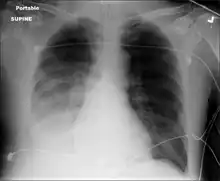

-

Chest X-ray pneumonia -

CT pneumonia -

X-ray pneumococcal osteomyelitis -

MRI pneumococcal osteomyelitis